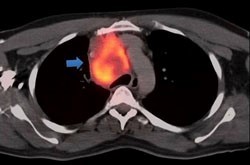

Παραδείγματα πότε μπορεί να βοηθήσει η εξέταση (ΕBUS) στη διάγνωση